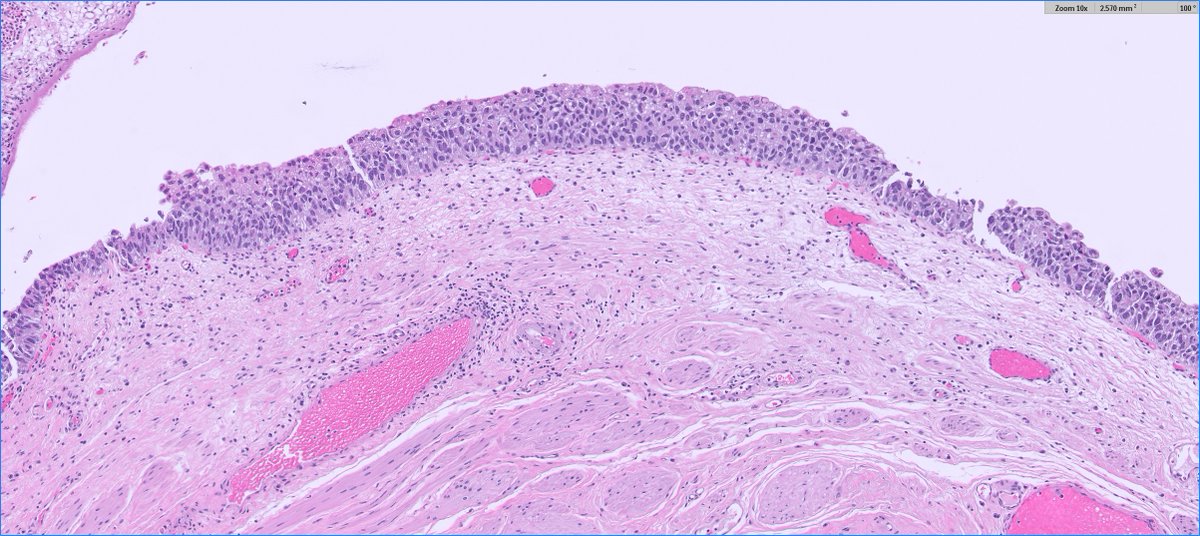

*** Case of the Month *** Bladder lesion in an 80 yr old female patient Contributors : Ronniel Morais Albuquerque Daniel Athanazio FB: GU Pathology Society IG: gu_pathology_society LinkedIN: GUPS Society Bluesky: https://t.co/1hR9PHdTaG

https://t.co/ijDfT9Juld